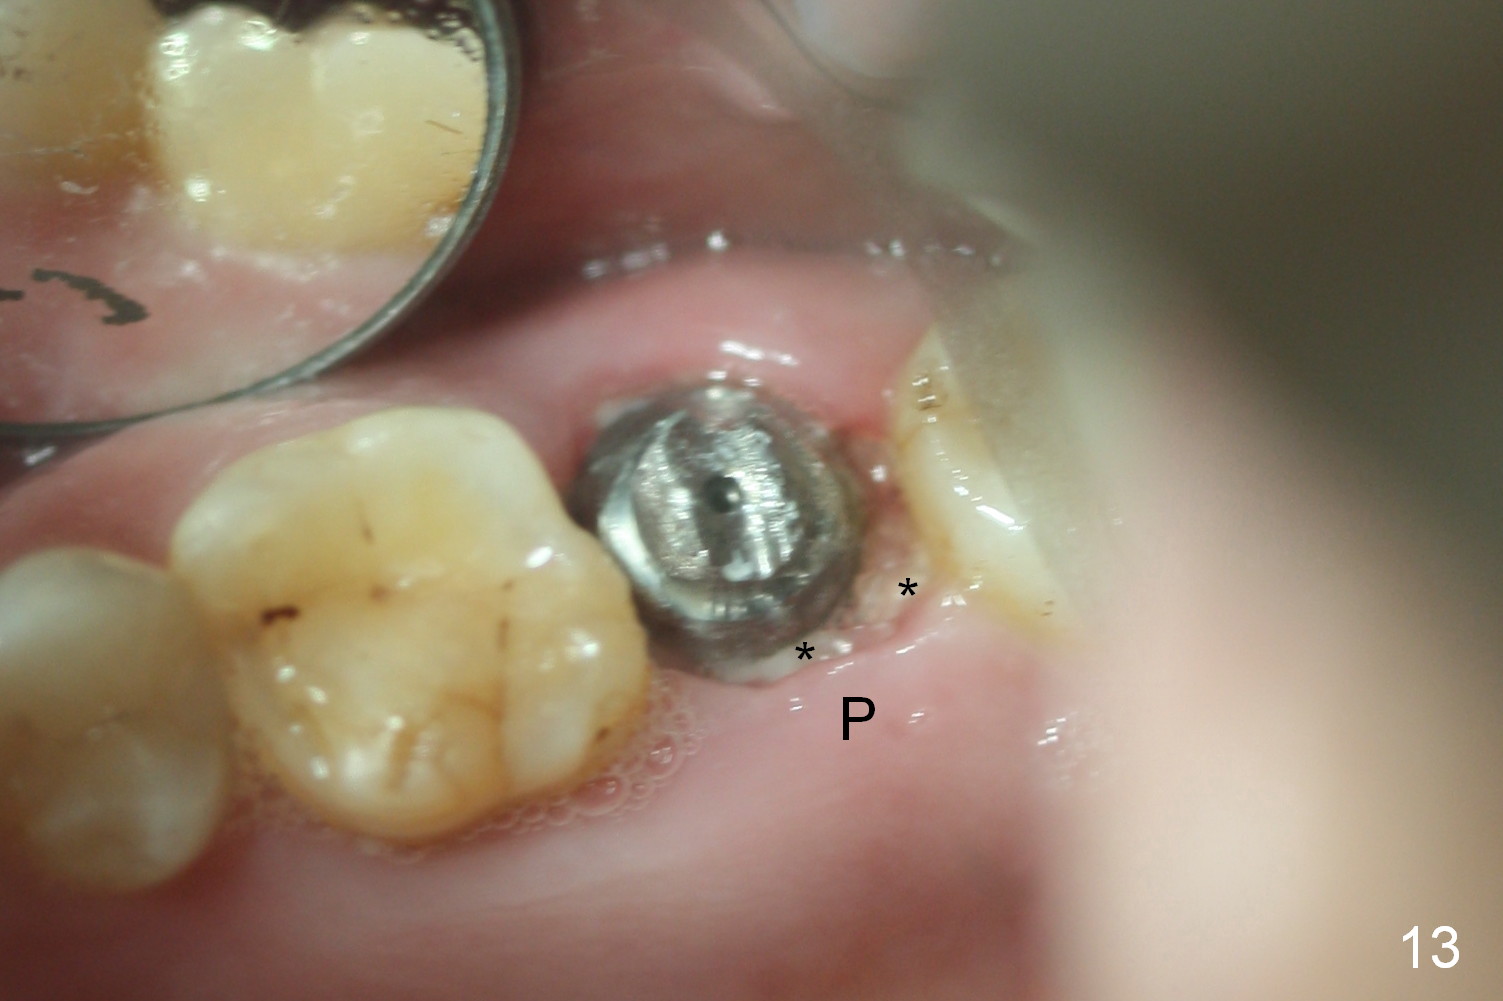

The patient returns because of provisional dislodgement 4 days postop. It appears that the socket shrinks (Fig.13 mirror view) with partial resolution of collagen dressing (*, as compared to Fig.10). The provisional is relined and reseated with occlusion checked (Fig.14). There is no sign or symptom of infection. The patient is pleased.